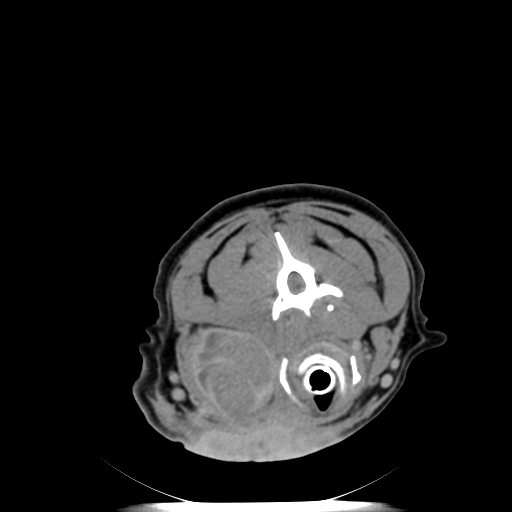

The VetTom 32 has a powerful 40 kW generator, 85 cm gantry, 60 cm field-of-view, scans using proprietary batteries and can be moved to where you need imaging, especially when it may be difficult to move the patient.